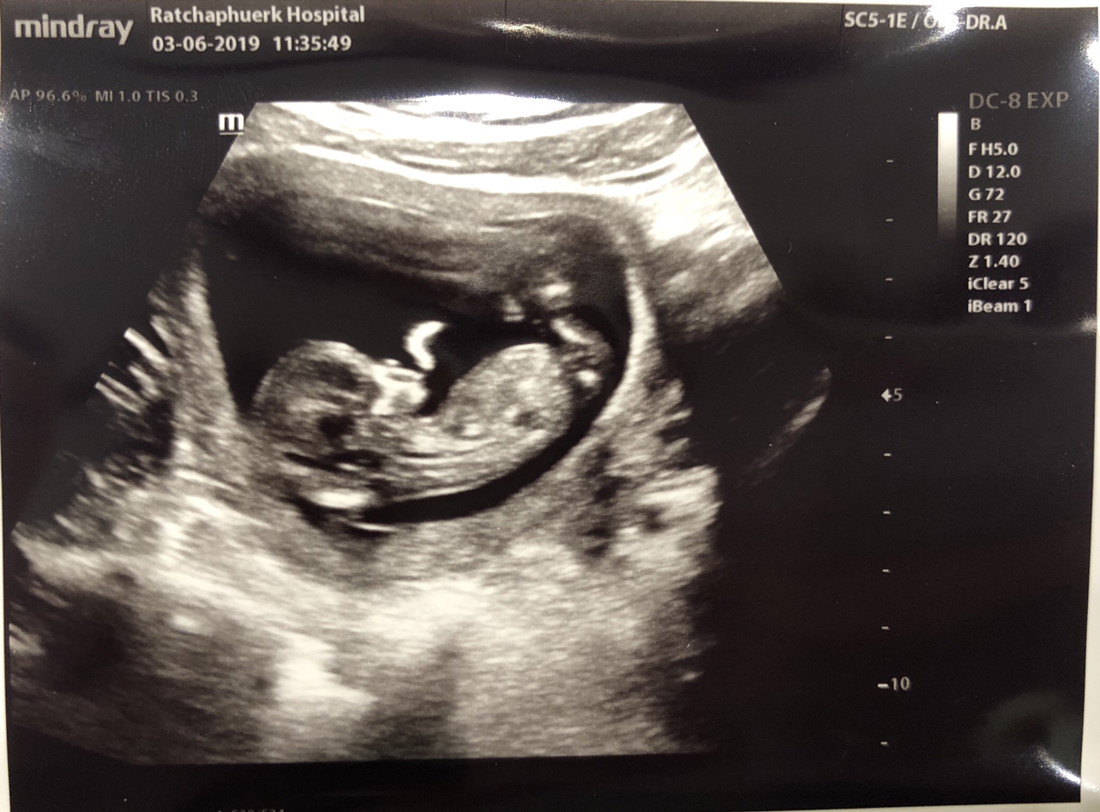

14ธันวาจ้า ซาวตอน17wค่า ไม่ยอมให้ดูเพศเลยนอนคว่ำสะงั้น